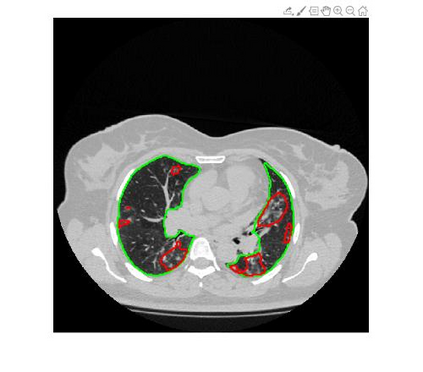

Since the breakout of coronavirus disease (COVID-19), the computer-aided diagnosis has become a necessity to prevent the spread of the virus. Detecting COVID-19 at an early stage is essential to reduce the mortality risk of the patients. In this study, a cascaded system is proposed to segment the lung, detect, localize, and quantify COVID-19 infections from computed tomography (CT) images Furthermore, the system classifies the severity of COVID-19 as mild, moderate, severe, or critical based on the percentage of infected lungs. An extensive set of experiments were performed using state-of-the-art deep Encoder-Decoder Convolutional Neural Networks (ED-CNNs), UNet, and Feature Pyramid Network (FPN), with different backbone (encoder) structures using the variants of DenseNet and ResNet. The conducted experiments showed the best performance for lung region segmentation with Dice Similarity Coefficient (DSC) of 97.19% and Intersection over Union (IoU) of 95.10% using U-Net model with the DenseNet 161 encoder. Furthermore, the proposed system achieved an elegant performance for COVID-19 infection segmentation with a DSC of 94.13% and IoU of 91.85% using the FPN model with the DenseNet201 encoder. The achieved performance is significantly superior to previous methods for COVID-19 lesion localization. Besides, the proposed system can reliably localize infection of various shapes and sizes, especially small infection regions, which are rarely considered in recent studies. Moreover, the proposed system achieved high COVID-19 detection performance with 99.64% sensitivity and 98.72% specificity. Finally, the system was able to discriminate between different severity levels of COVID-19 infection over a dataset of 1,110 subjects with sensitivity values of 98.3%, 71.2%, 77.8%, and 100% for mild, moderate, severe, and critical infections, respectively.